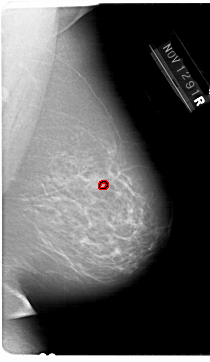

A_1648_1.RIGHT_CC

RIGHT_CC LINES 6301 PIXELS_PER_LINE 3376 BITS_PER_PIXEL 12 RESOLUTION 43.5 OVERLAY

FILE: A_1648_1.RIGHT_CC.OVERLAY

TOTAL_ABNORMALITIES 1

ABNORMALITY 1

LESION_TYPE CALCIFICATION TYPE PLEOMORPHIC DISTRIBUTION CLUSTERED

ASSESSMENT 4

SUBTLETY 2

PATHOLOGY BENIGN

TOTAL_OUTLINES 1

BOUNDARY